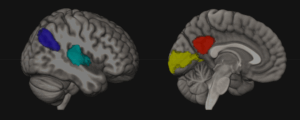

Parents activate brain regions linked with social cognition, reward processing, and emotion when viewing their own infant. Neural responses to own-infant stimuli may be driven by familiarity, self-relevance, or by the unique features of infant faces. The current study sought to clarify these distinctions in first-time fathers by contrasting video stimuli of their infant, an unfamiliar infant, and their pregnant partner.